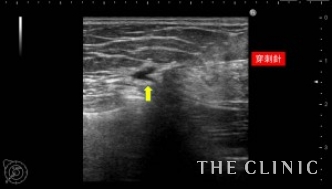

この方は、10年前に脂肪注入を受けられていて、近年の乳がん検診にてしこりを指摘されたとのこと。指摘後は何もせず放置していたが、昨年ぐらいから自分でもしこりを感じるようになったため、当院を受診されました。

しこりの大きさは3mmから7mmと非常に小さなしこりでしたが、ご本人が治療を希望されたためエコー下に穿刺吸引しました。右のしこりの1つは乳腺内の腫瘤でしたが濃縮のう胞でした。

吸引した脂肪です。両側合わせて12個のオイルシストを穿刺吸引しました。